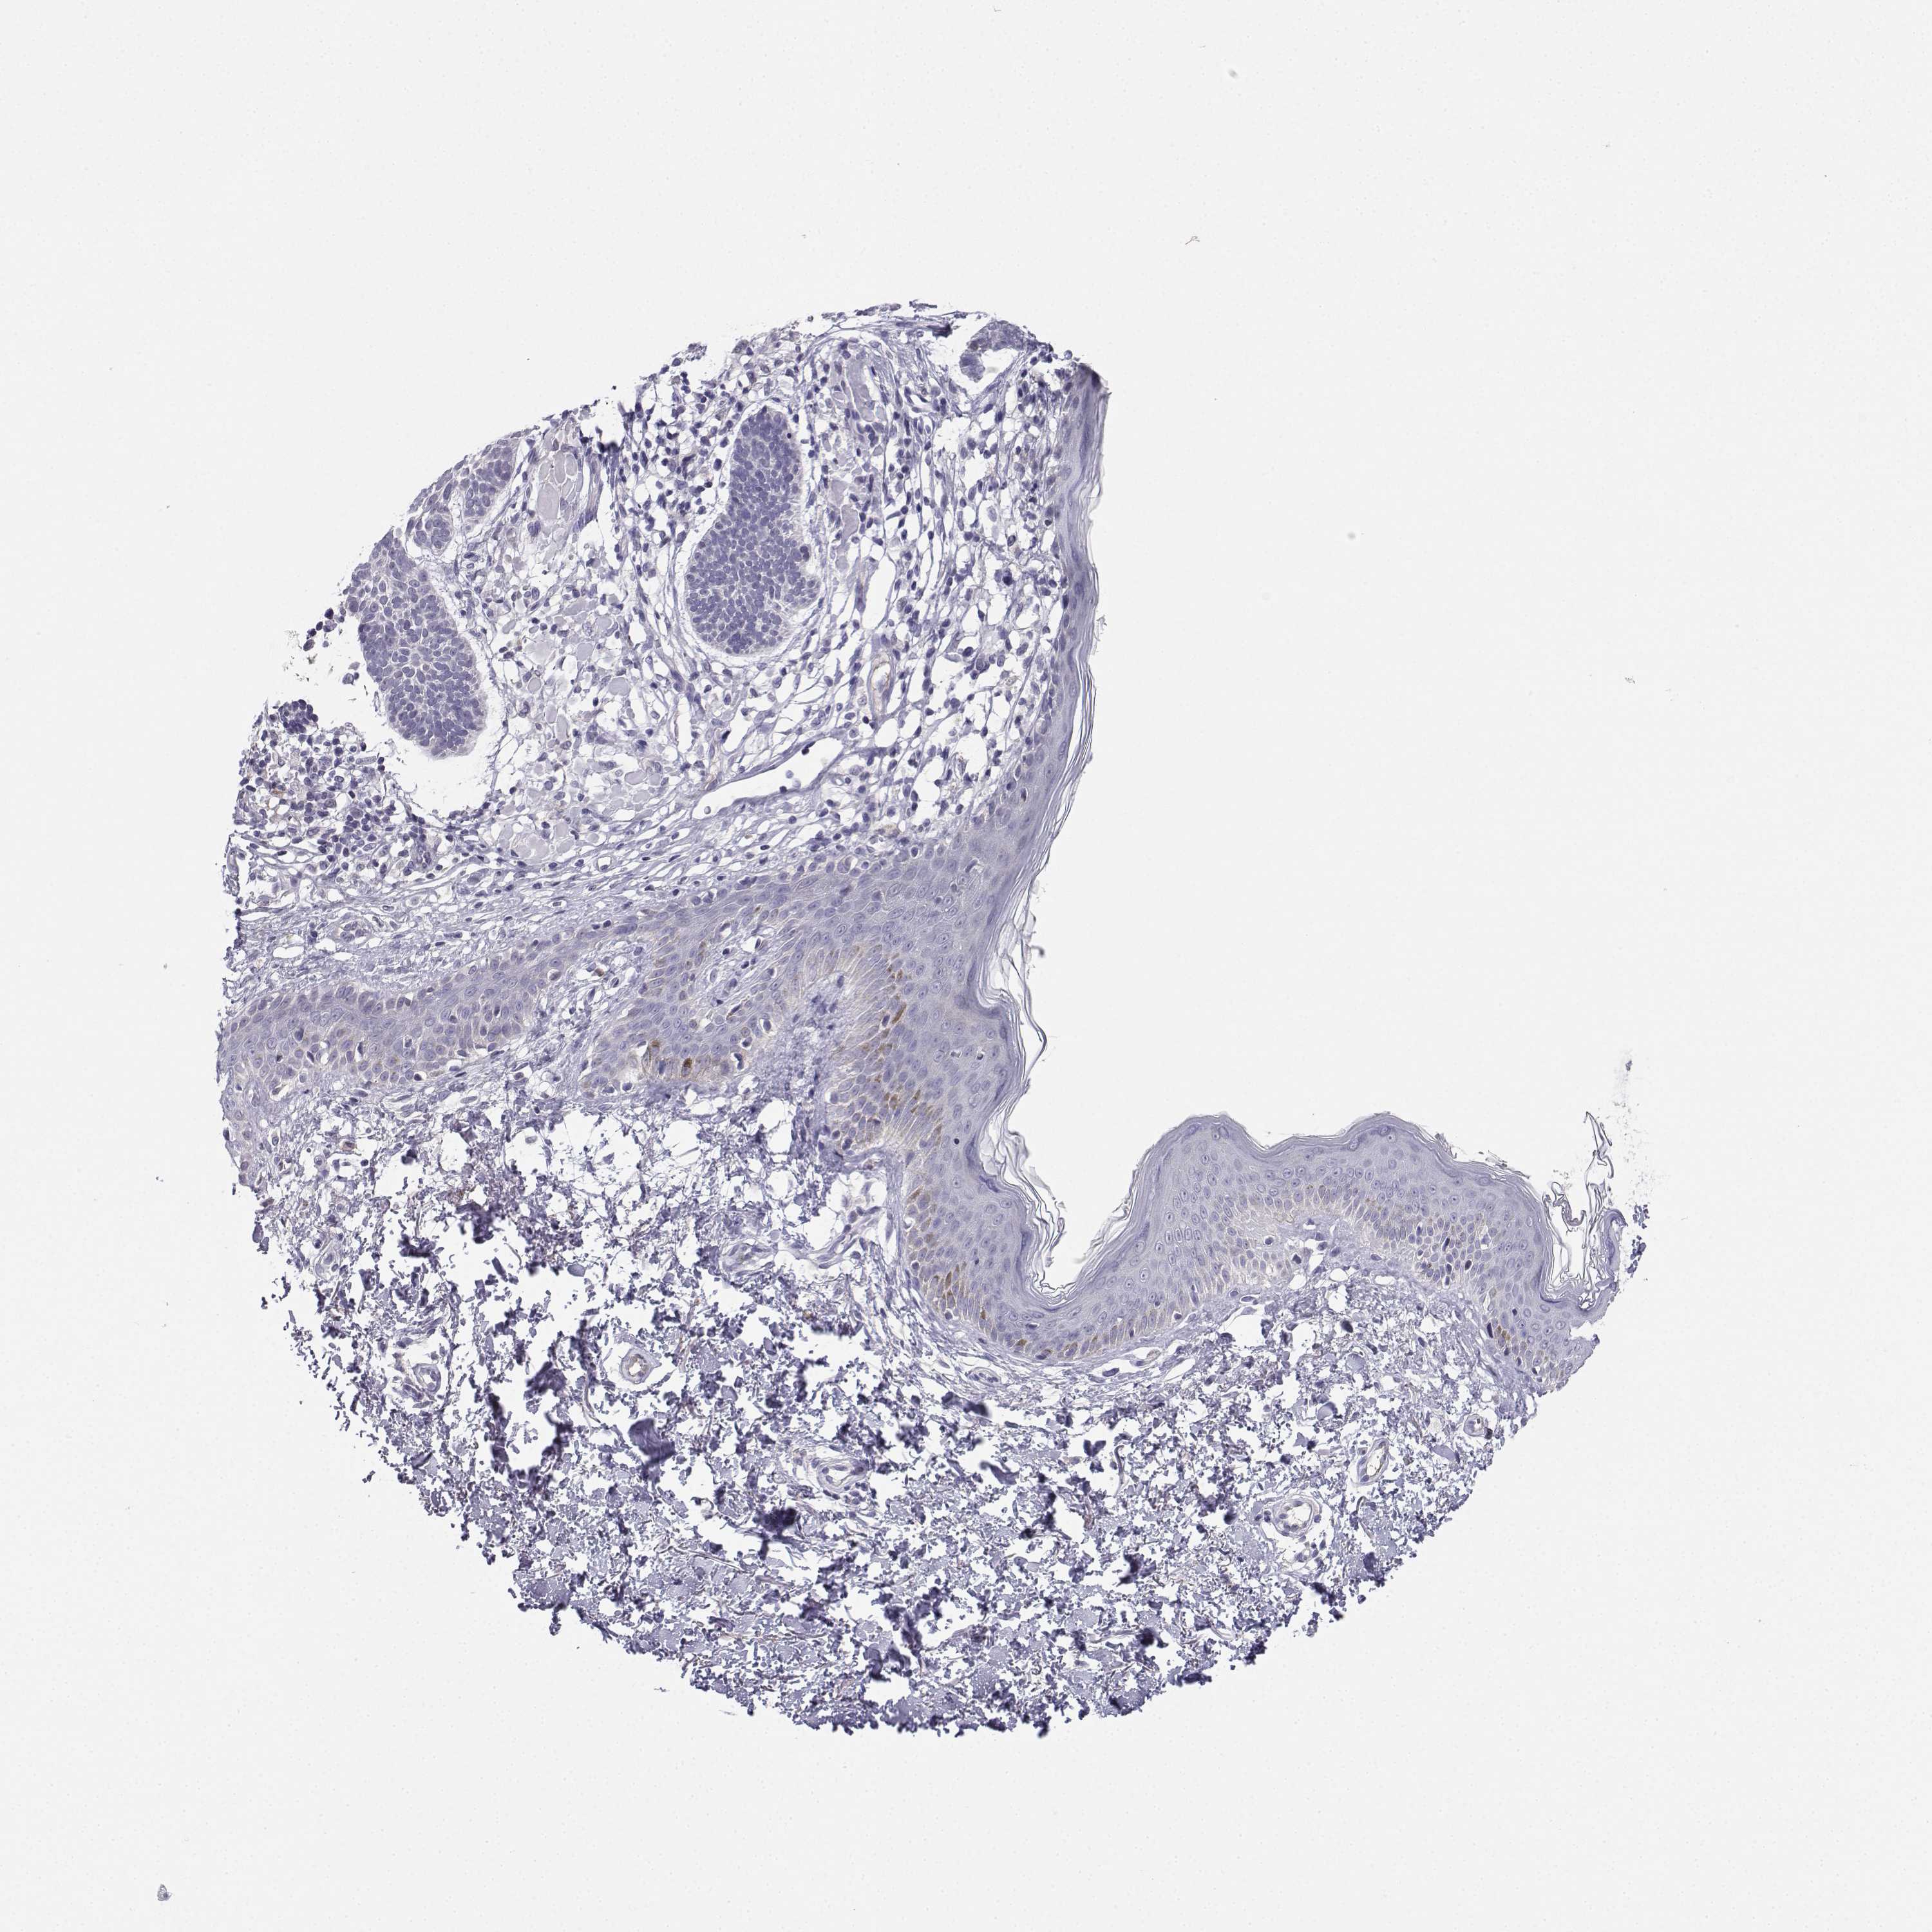

SKIN CANCER - Protein expressioni

A mouse-over function shows sample information and annotation data. Click on an image to view it in a full screen mode. Samples can be filtered based on level of antibody staining by selecting one or several of the following categories: high, medium, low and not detected. The assay and annotation is described here.

Antibody stainingi

Antibody staining in the annotated cell types in the current human tissue is reported as not detected, low, medium, or high, based on conventional immunohistochemistry profiling in selected tissues. This score is based on the combination of the staining intensity and fraction of stained cells.

Each image is clickable and will lead to virtual microscopy that enables deeper exploration of all samples and also displays staining intensity scores, fraction scores and subcellular localization as well as patient and tissue information for each sample.

Antibody HPA042283

Staining

High

Medium

Low

Not detected

Intensity

Strong

Moderate

Weak

Negative

Quantity

>75%

75%-25%

<25%

None

Location

Nuclear

Cytoplasmic/membranous

Cytoplasmic/membranous,nuclear

Basal cell carcinoma

Squamous cell carcinoma, NOS